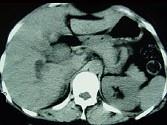

问题 女,35岁,右上腹痛1月,黄疸进行性加重,AFP阴性,消瘦乏力,影像检查如图,最可能的诊断为()

选项 A.肝转移癌 B.胆管癌 C.局灶性脂肪肝 D.原发性肝癌 E.肝血管瘤

答案 B